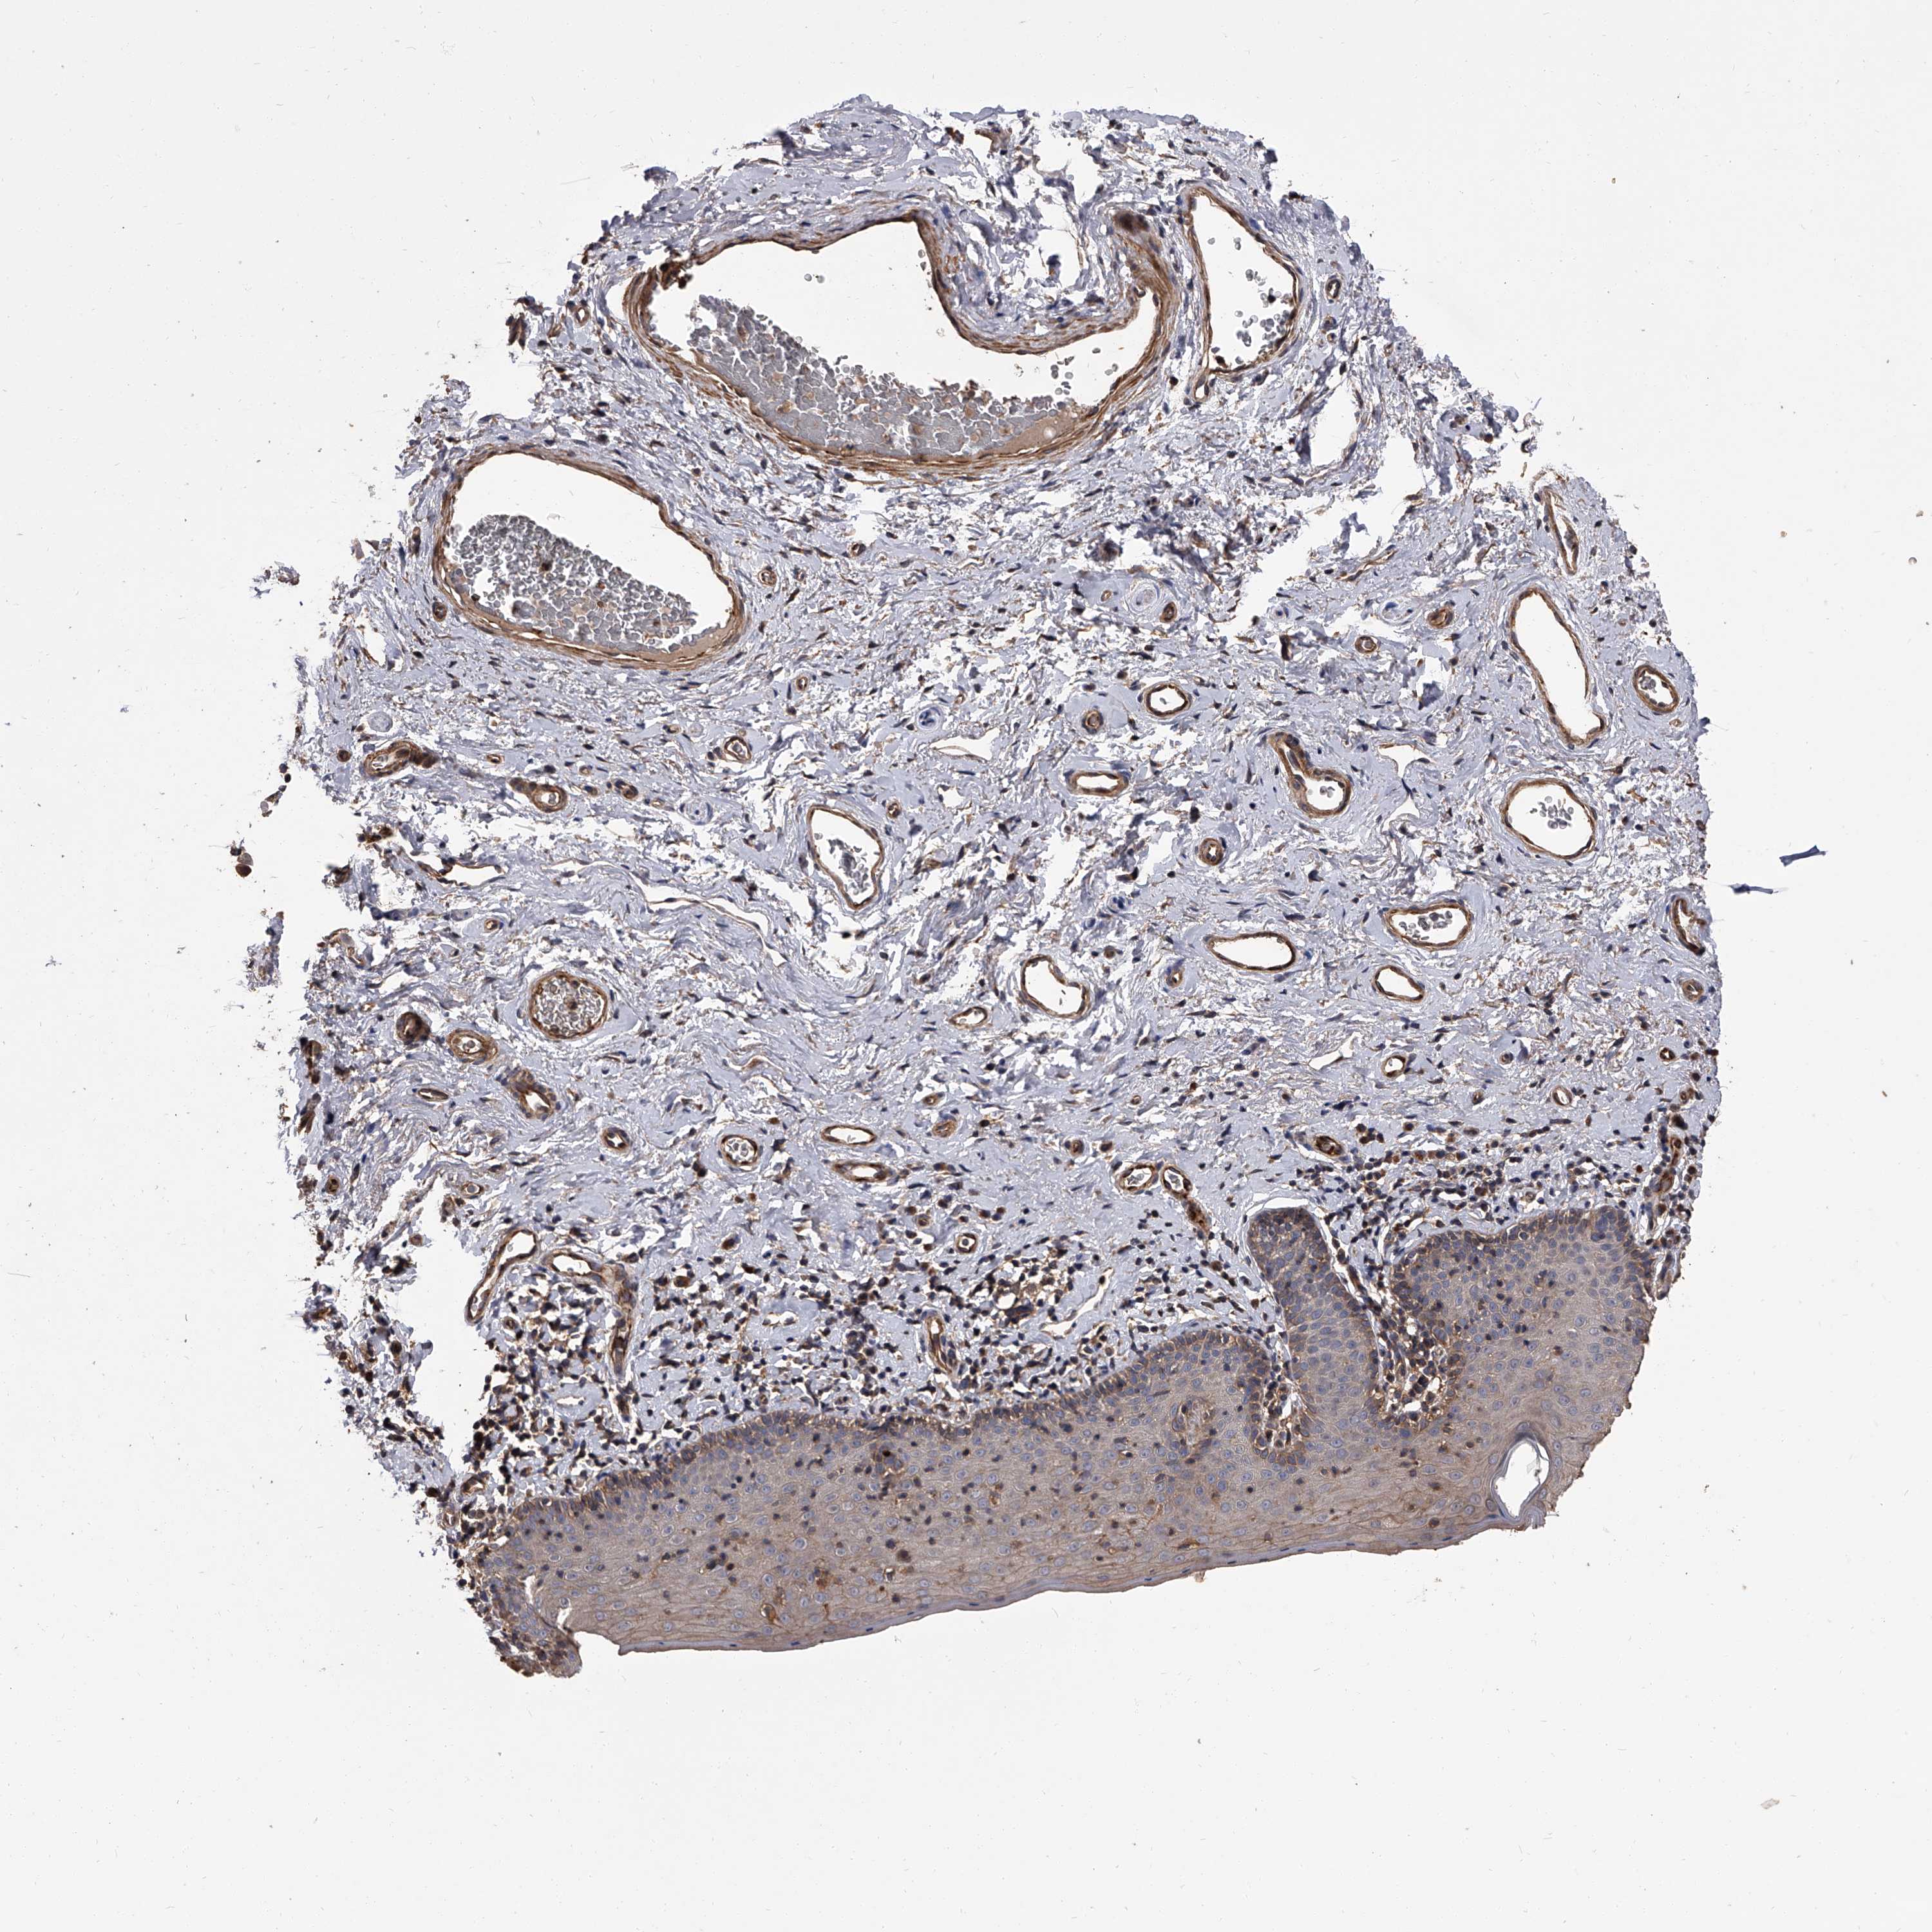

SKIN 2 - Antibody stainingi

Antibody staining in the annotated cell types in the current human tissue is reported as not detected, low, medium, or high, based on conventional immunohistochemistry profiling in selected tissues. This score is based on the combination of the staining intensity and fraction of stained cells.

Each image is clickable and will lead to virtual microscopy that enables deeper exploration of all samples and also displays staining intensity scores, fraction scores and subcellular localization as well as patient and tissue information for each sample.

Antibody HPA027409Antibody HPA027453Antibody HPA030058

Epidermal cells MediumMediumNot detected